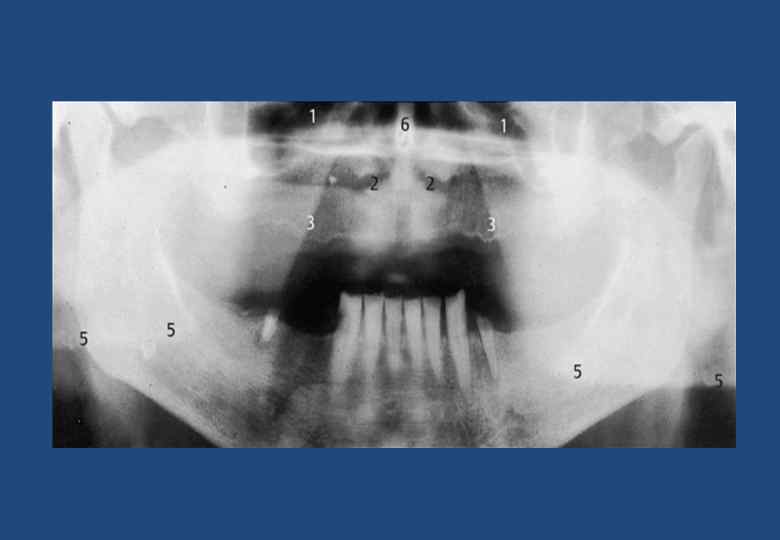

• • • • • • 1. Глазница 2. Шейные отдел позвоночника и зуб второго шейного позвонка 3. Компактный слой вещества в основании противоположной половины челюсти 4. Перегородка носа 5. Нижняя носовая раковина 6. Верхнечелюстная пазуха 7. Передний носовой гребень 8. Горизонтальная пластинка небной кости 9. Боковая стенка полости носа 10. Небная занавеска 11. Крыловидно-небная ямка 12. Тело скуловой кости с безымянной линией 13. Скуловая дуга 14. Компактное вещество тела нижней челюсти 15. Челюстно-подъязычная линия 16. Канал нижней челюсти 17. Подбородочное отверстие канала нижней челюсти 18. Двубрюшная или подбородочная ямка 19. Ушная раковина с отверстием наружного слухового прохода 20. Мыщелковый отросток нижней челюсти 21. Венечный отросток нижней челюсти 22. Шиловидный отросток височной кости 23. Подъязычная кость 24. Основание языка